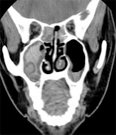

La TC mostra l’interessamento sia mucoso che osseo dei seni paranasali da parte dell’infezione micotica, in tal caso particolarmente aggressiva e con frequente estensione orbitaria ed endocranica (fossa cranica anteriore e media), con caratteristiche e patognomoniche calcificazioni endosinusali. La RMN è caratterizzata anche in questo caso dalla assenza di segnale e può contribuire, in tal senso alla diagnosi differenziale con le forme neoplastiche.